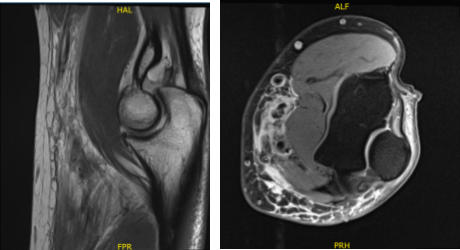

For previous surgery, he reported none. The patient’s MRI result was reviewed and discussed. The results showed biceps tendon rupture and lateral epicondylitis.

MRI 3T Left Elbow non-contrast